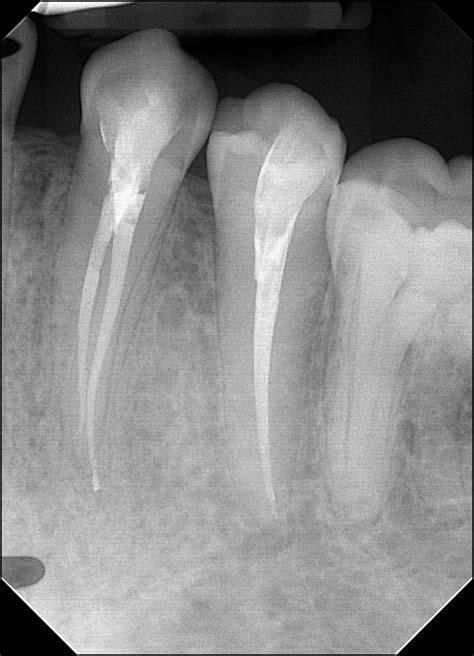

1. Diagnosis and Anesthesia: Your dentist will take X-rays to assess the extent of the infection. Local anesthesia is administered to ensure you do not feel pain during the treatment.

The pulp inside your tooth is vital during its development, but once a tooth is fully mature, it can survive without the pulp if the surrounding tissues remain healthy. An Rct of teeth is indicated when the pulp becomes inflamed or infected due to deep decay, repeated dental procedures on the same tooth, or traumatic injuries. If left untreated, the infection can spread, leading to abscesses, bone loss, and severe pain.